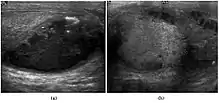

Teratoma Although teratoma is the second most common testicular tumor in children, it affects all age groups. Mature teratoma in children is often benign, but teratoma in adults, regardless of age, should be considered malignant. Teratomas are composed of all three germ cell layers, i.e. endoderm, mesoderm and ectoderm. At ultrasound, teratomas generally form well-circumscribed complex masses. Echogenic foci representing calcification, cartilage, immature bone and fibrosis are commonly seen [Fig. 5]. Cysts are also a common feature and depending on the contents of the cysts i.e. serous, mucoid or keratinous fluid, it may present as anechoic or complex structure [Fig. 6].

![Fig. 6. Mature cystic teratoma. (a) Composite Image. Mature cystic teratoma in a 29-year-old man. Longitudinal sonography image of the right testis shows a multilocular cystic mass. (b) Mature cystic teratoma in a 6-year-old boy. Longitudinal sonography of the right testis shows a cystic mass containing calcification with no obvious acoustic shadow.[citation needed]](../I/Ultrasonographies_of_mature_cystic_teratomas.jpg.webp) Fig. 6. Mature cystic teratoma. (a) Composite Image. Mature cystic teratoma in a 29-year-old man. Longitudinal sonography image of the right testis shows a multilocular cystic mass. (b) Mature cystic teratoma in a 6-year-old boy. Longitudinal sonography of the right testis shows a cystic mass containing calcification with no obvious acoustic shadow. Fig. 6. Mature cystic teratoma. (a) Composite Image. Mature cystic teratoma in a 29-year-old man. Longitudinal sonography image of the right testis shows a multilocular cystic mass. (b) Mature cystic teratoma in a 6-year-old boy. Longitudinal sonography of the right testis shows a cystic mass containing calcification with no obvious acoustic shadow.